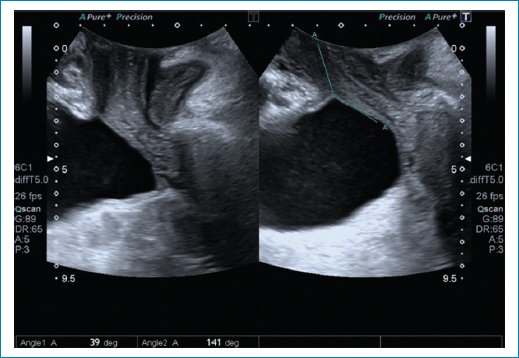

• – En Valsalva también podemos medir:

• Ángulo de rotación de la uretra: rotación postero-inferior de la uretra que apoya el diagnóstico de hipermovilidad uretral (Fig. 9).

Figura 9. Se observa la medición del ángulo de rotación de la uretra, mayor a 30 grados, que apoya al diagnóstico de hipermovilidad uretral.